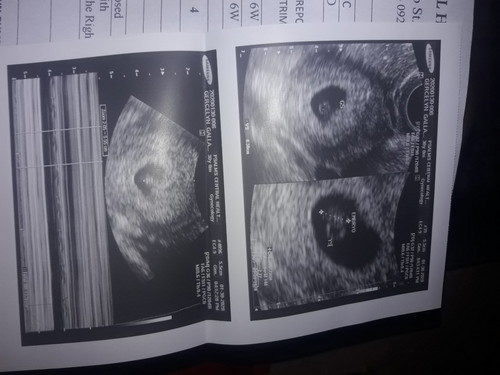

Nagpacheck up nanaman ako...? bakit kaya nagbago yung EDD ko??? Dati sept 22 ngayon sept 20 na? pero happy ako ngayon kasi kahit nagsspotting ako may heart beat na daw baby ko?❤.... yun lang di pa rin ako binigyan ng fit to work? pero ok lang mas importante si baby... nagyon 6 weeks and 4 days na sya. Eh mga mamsh ano ba ibig sabihin don sa comment ni dra na: In the uterus is well-decidualized gestational sac, a yolk sac and an embryo with cardiac activity....